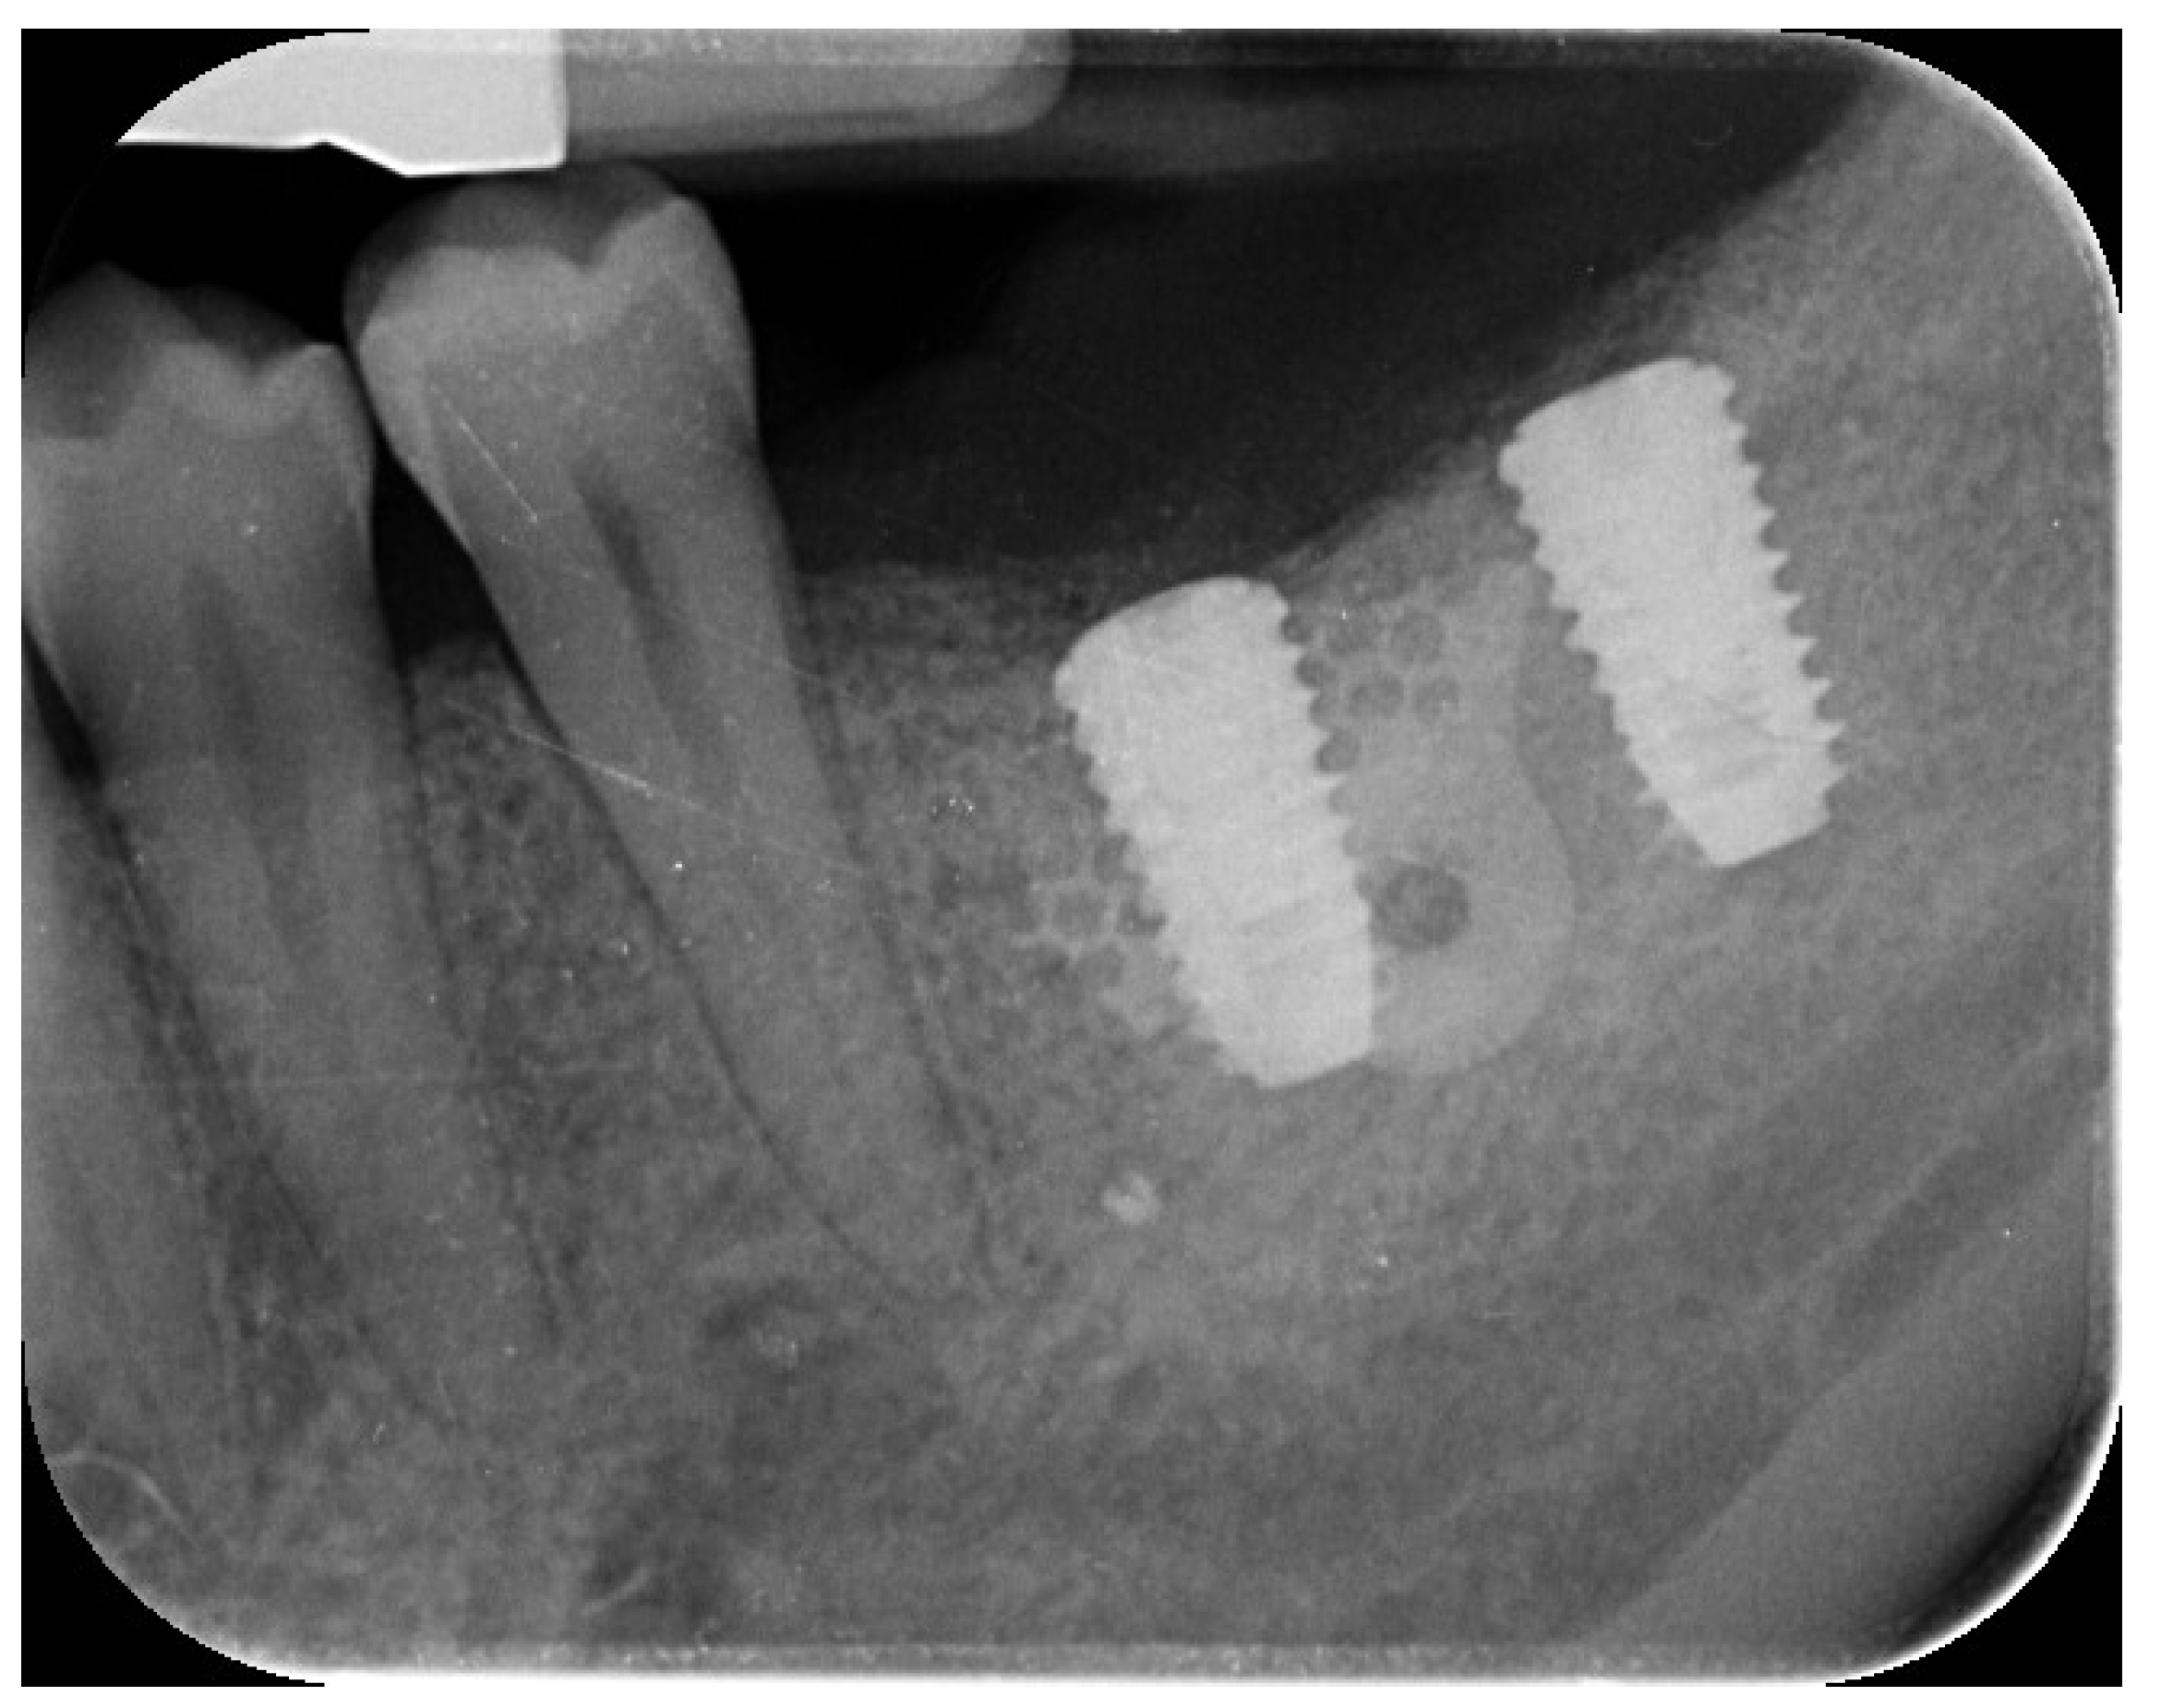

2. Case Summary